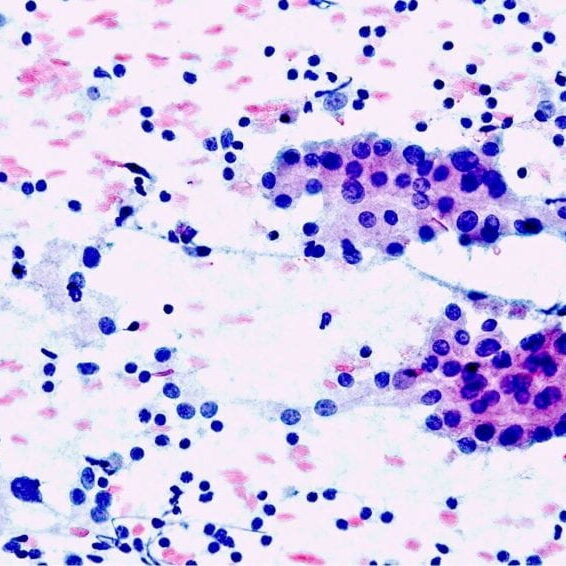

Welcome to the world of cytopathology!

for pathology residents and cytotechnologists, welcome to our cytopathology pages!

Interesting cases illustrated here from across different body system